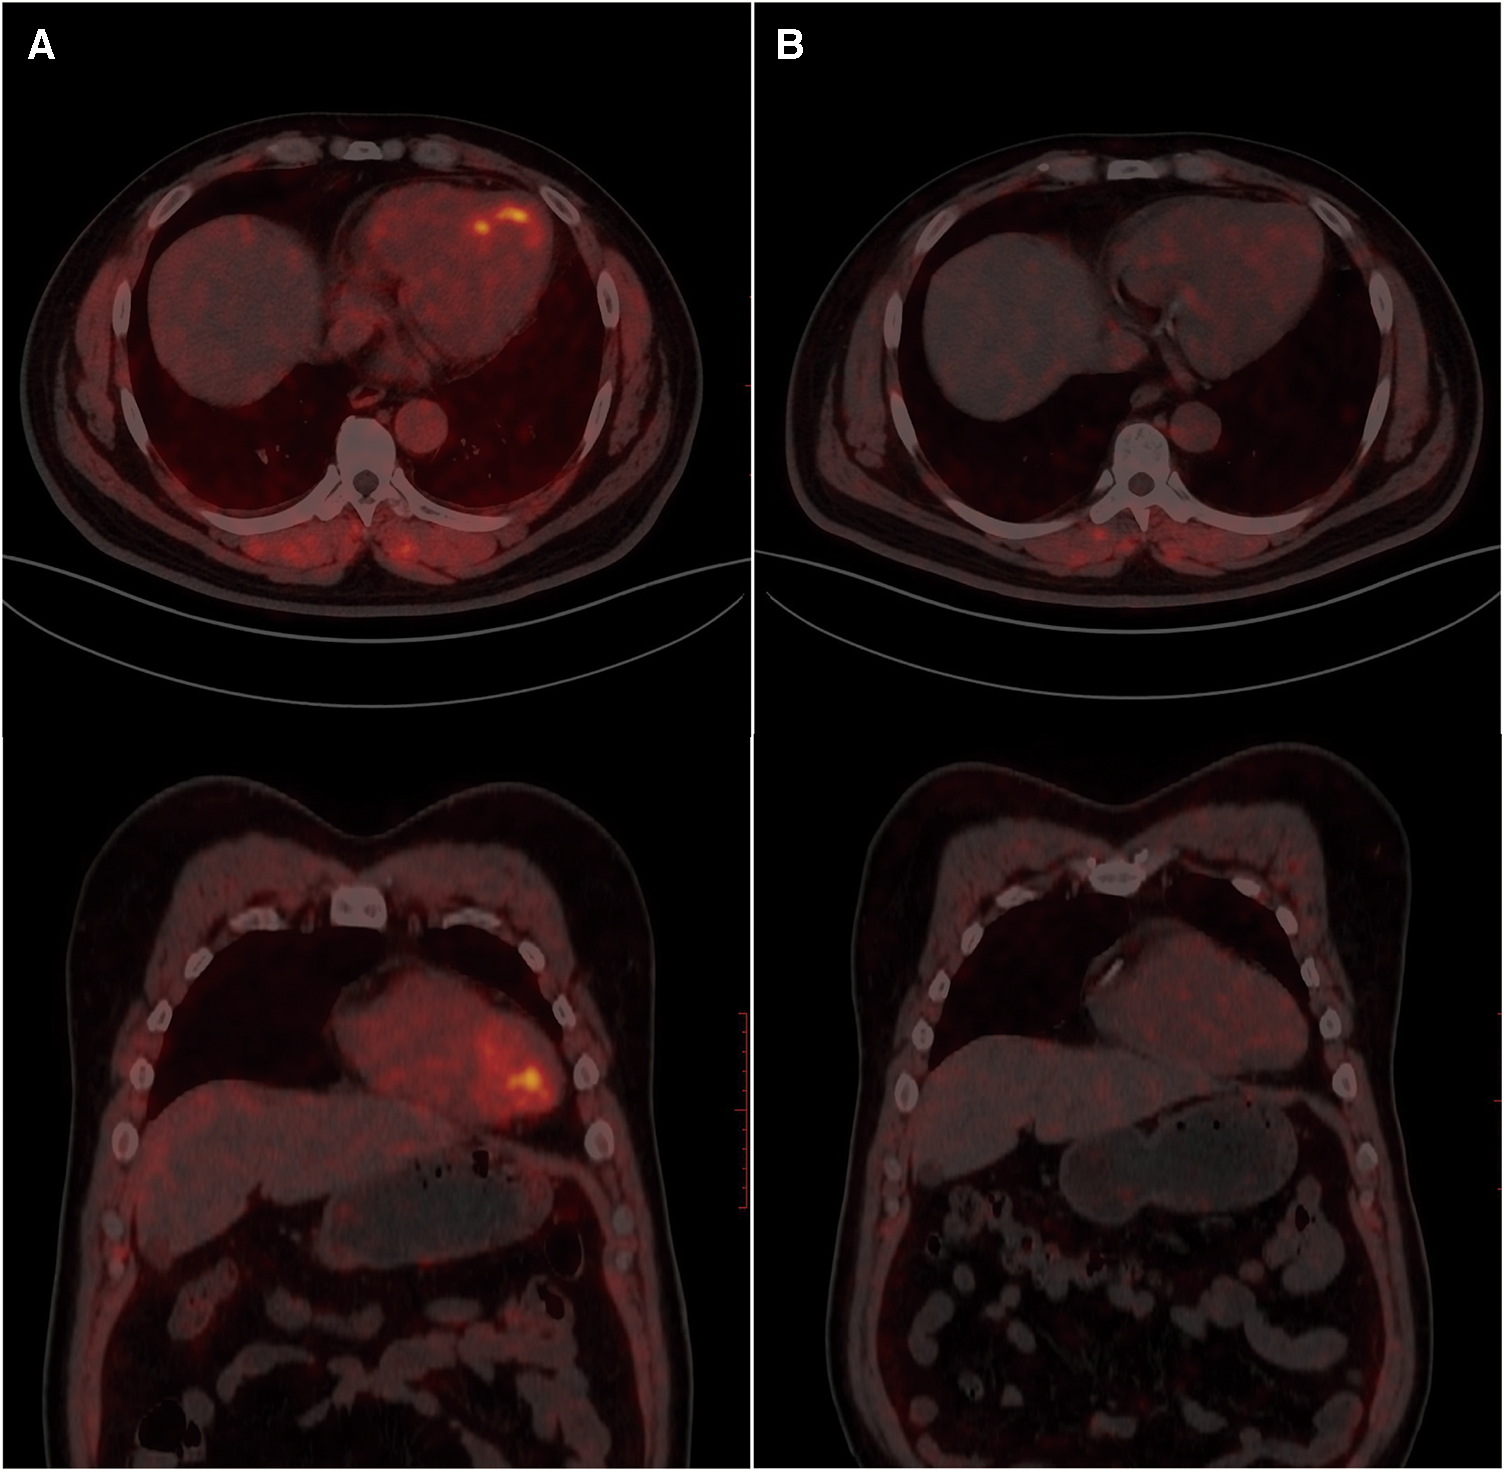

To evaluate the patient's myocardial fibrosis, a 68Ga-FAPI-04 PET/CT examination was conducted the day following the first stage PCI (Figure 2A). The results revealed elevated FAPI uptake in the left ventricular myocardium, specifically in the apex, anterior wall, and septum, with an SUVmax (maximum standard uptake value) of approximately 4.6, consistent with the distribution of the LAD. Considering the link between ischemia and active fibroblast in pathophysiology, we hypothesize that the LAD is more likely to be the “culprit vessel” during the patient's angina attacks, while the RCA and LCX may be considered as “bystanders.” Subsequently, the patient daily received aspirin 100 mg and ticagrelor 180 mg for antiplatelet aggregation therapy, atorvastatin 20 mg and hybutimibe 10 mg for hypolipidemic therapy, sacubitril/valsartan 100 mg for antihypertensive therapy, and levothyroxine sodium tablets 50 μg for thyroid hormone supplementation. During follow-up, the patient remained free of chest pain, adhered to medication, and maintained blood pressure within the range of 120–130/70–80 mmHg.

Figure 2

68Ga-FAPI-04 PET/CT myocardial imaging. A. Examination results one day after postoperative PCI. B. Follow-up examination results after two months.

Two months later, the patient's ECG was normal (Figure 1A), cardiac injury markers and thyroid function were normal, and there was some improvement in dyslipidemia (low-density lipoprotein 1.36 mmol/L, high-density lipoprotein 1.06 mmol/L, total cholesterol 2.87 mmol/L, triglycerides 2.15 mmol/L). A follow-up 68Ga-FAPI PET/CT examination (Figure 2B) revealed a slight increase in FAP expression in a smaller localized area of the left ventricular apex, with an SUVmax of approximately 1.8. The rest of the myocardium exhibited uniform tracer uptake similar to blood pool activity. Compared to the initial examination, the extent of 68Ga-FAPI04 uptake in the left ventricular myocardium significantly decreased, and the SUVmax notably reduced. Meanwhile, echocardiographic measurements showed mild enlargement of the left ventricle within the normal range, with unaffected systolic function (Table 1).

The radiotracer 68Ga-FAPI-04 can selectively target FAP and visualize activated fibroblasts. In this case, the left ventricular myocardium displayed focal uptake of 68Ga-FAPI-04 (SUVmax = 4.6), indicating the detection of active fibroblasts caused by transient myocardial ischemia was sensitive. Compared to previous studies on MI, the myocardial uptake in the UA patient was lower, potentially indicating a correlation with the extent of myocardial damage (10).

After a 2-month follow-up, a repeat 68Ga-FAPI-04 PET/CT revealed a significant decrease in tracer uptake in the previously affected area, without new uptake sites. The echocardiogram revealed mild left ventricular enlargement at the same time. Notably, healthy myocardium and mature myocardial scars, lacking active fibroblasts, do not exhibit uptake of 68Ga-FAPI-04 (11). This suggests that 68Ga-FAPI-04 PET/CT can provide early information on myocardial fibrosis, and has a certain predictive effect on ventricular remodeling, serving as a supplementary tool to traditional exams. On the other hand, 68Ga-FAPI-04 PET/CT provides insights into treatment efficacy by assessing activated fibroblasts. The patient underwent interventional therapy to address vascular narrowing and received pharmaceutical intervention for thrombosis prevention and the management of coronary risk factors, including hyperlipidemia, hypertension, andhypothyroidism. Upon reevaluation, the absence of newly activated fibroblasts suggested no recent myocardial ischemic damage, further supporting the treatment's effectiveness. In contrast, according to another study, it has been observed that a single case showed detectable high expression of FAP even 2 months after acute myocardial infarction. This difference may be associated with the distinct disease stages that the patients are in (acute phase and relatively stable phase) as well as the complete relief of myocardial ischemia (12). Therefore, more extensive cohort studies are warranted to explore further the degree, development, and outcome of myocardial fibrosis activated by different degrees of myocardial ischemia.